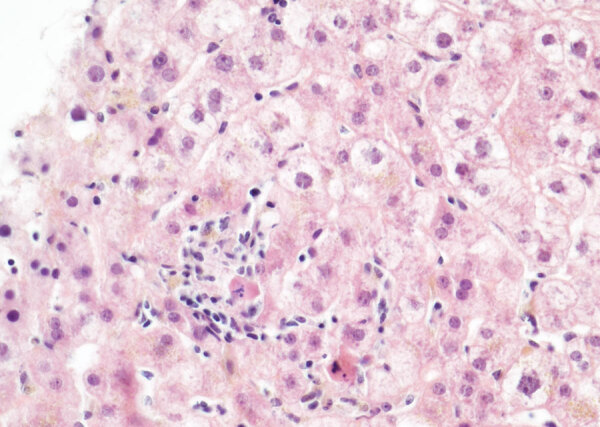

Description:In March 2022, a 61-year-old woman in France who had received a heart-lung transplant sought treatment with chronic hepatitis mainly characterized by increased liver enzymes. After ruling out common etiologies, we used metagenomic next-generation sequencing to analyze a liver biopsy sample and identified an unknown species of circovirus, tentatively named human circovirus 1 (HCirV-1). We found no other viral or bacterial sequences. HCirV-1 shared 70% amino acid identity with the closest known viral sequences. The viral genome was undetectable in blood samples from 2017-2019, then became detectable at low levels in September 2020 and peaked at very high titers (10| genome copies/mL) in January 2022. In March 2022, we found >10| genome copies/g or mL in the liver and blood, concomitant with hepatic cytolysis. We detected HCirV-1 transcripts in 2% of hepatocytes, demonstrating viral replication and supporting the role of HCirV-1 in liver damage.